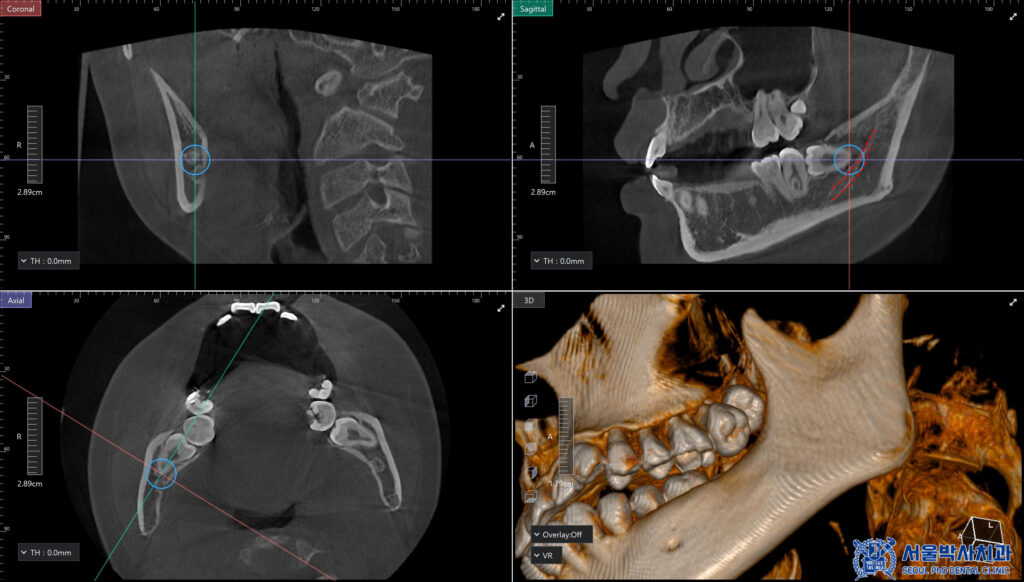

사랑니는 개인에 따라 매복 상태나

신경과의 위치가 달라

정밀한 진단이 중요하기 때문에,

3D CT를 촬영하여 사랑니의 위치와 형태,

주변 신경과의 거리 등을

정밀하게 확인했습니다.

이를 바탕으로 발치 과정에서

발생할 수 있는 위험 요소를

사전에 파악하고,

보다 안정적인 사랑니 발치를

계획하였습니다.